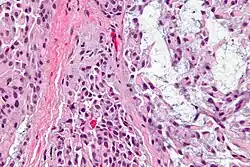

Myoepithelial cells (sometimes referred to as myoepithelium) are cells usually found in glandular epithelium as a thin layer above the basement membrane but generally beneath the luminal cells. These may be positive for alpha smooth muscle actin and can contract and expel the secretions of exocrine glands. They are found in the sweat glands, mammary glands, lacrimal glands, and salivary glands. Myoepithelial cells in these cases constitute the basal cell layer of an epithelium that harbors the epithelial progenitor. In the case of wound healing, myoepithelial cells reactively proliferate. Presence of myoepithelial cells in a hyperplastic tissue proves the benignity of the gland and, when absent, indicates cancer. Only rare cancers like adenoid cystic carcinomas contains myoepithelial cells as one of the malignant components.

Myoepithelial cells are true epithelial cells positive for keratins, not to be confused with myofibroblasts which are true mesenchymal cells positive for vimentin. These cells are generally positive for alpha smooth muscle actin (αSMA), cytokeratin 5/6 and other high molecular weight cytokeratins, p63 and caldesmon. Myoepithelial cells are stellate in shape and are also known as basket cells. They lie between the basement membrane and glandular epithelium. Each cell consists of a cell body from which 4-8 processes radiate and embrace the secretory unit. Myoepithelial cells have contractile functions. They help in expelling secretions from the lumen of secretory units and facilitate the movement of saliva in salivary ducts.